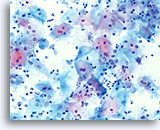

Shift in the Flora Suggestive of Bacterial Vaginosis

Squamous cells may be covered with coccobacilli when the normal lactobacilli are absent. A diagnosis of bacterial vaginosis may be confirmed by bacterial culture.

Chronic Follicular Cervicitis

The presence of lymphocytes accompanied by tingible body macrophages may indicate a chronic inflammatory condition or the rupturing of a lymph follicle during sample collection. On the ThinPrep slide the lymphocytes from chronic follicular cervicitis will generally appear in small clusters grouped together. The presence of tingible body macrophages aid in the diagnosis.